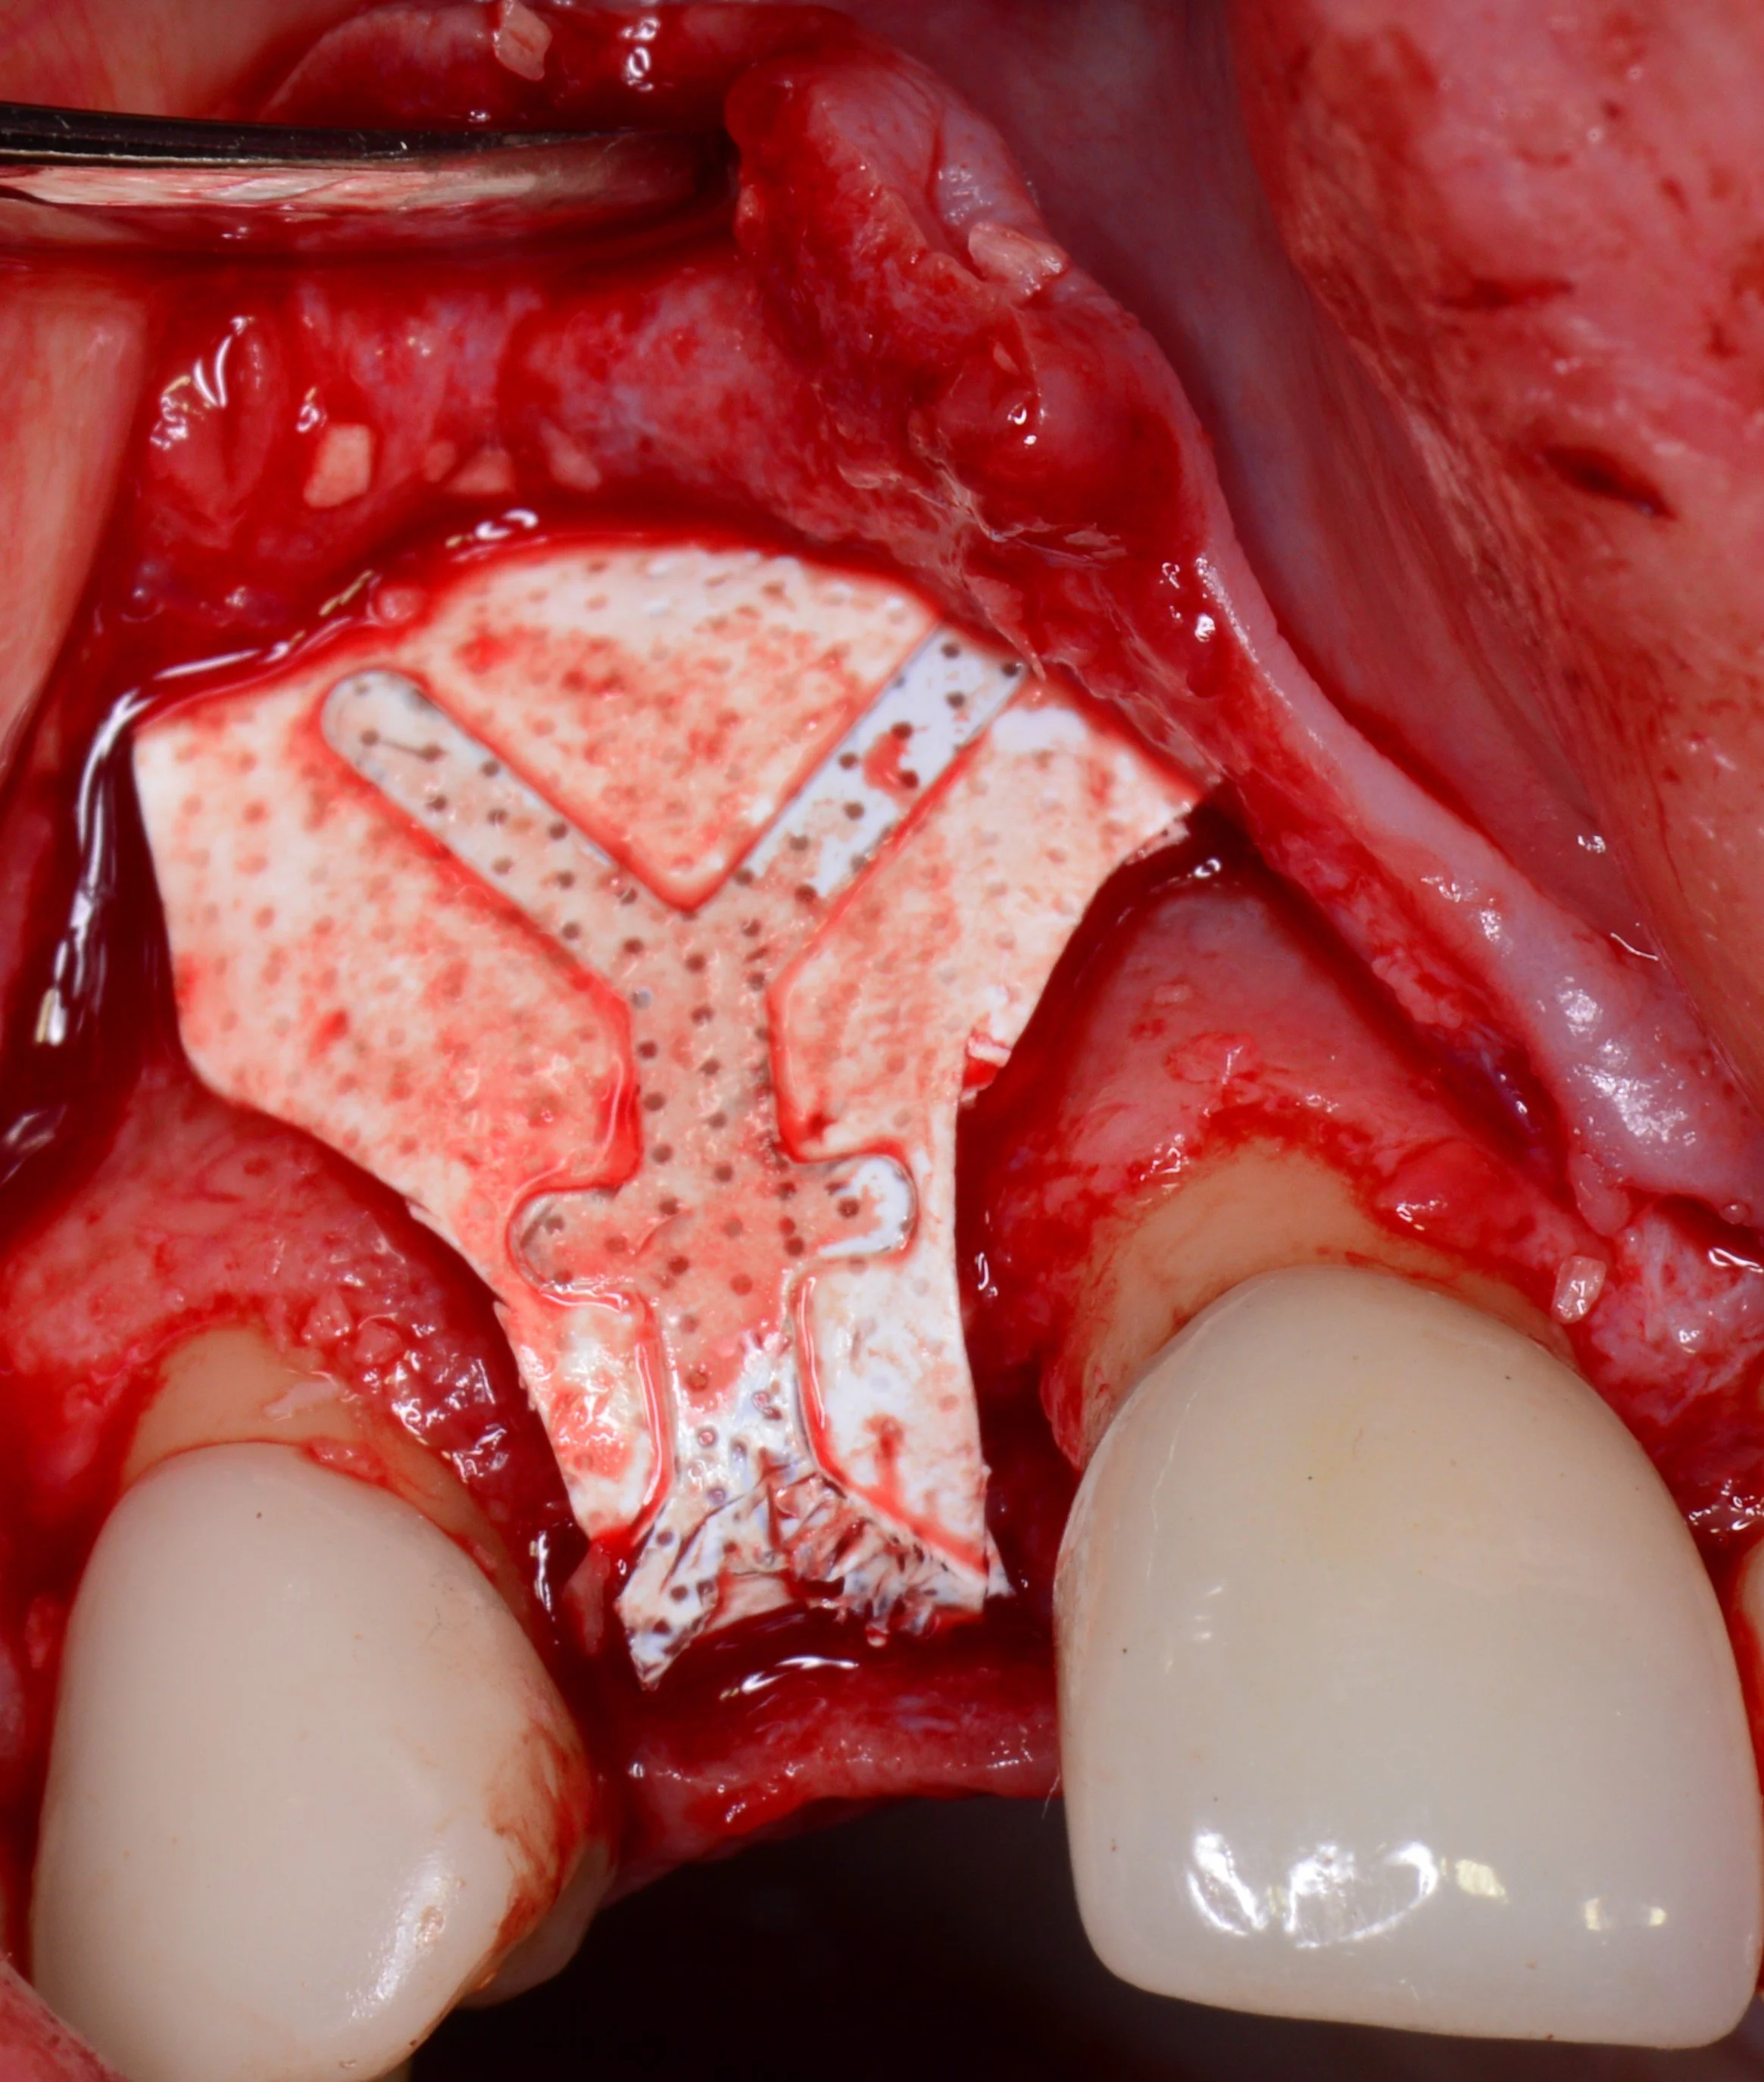

2. Protection: A small, dissolvable or removable membrane is placed over the graft to keep gum tissue out and let bone cells grow undisturbed.

3. Integration: Over the next 3 to 6 months, your body naturally replaces the grafting material with your own living bone.